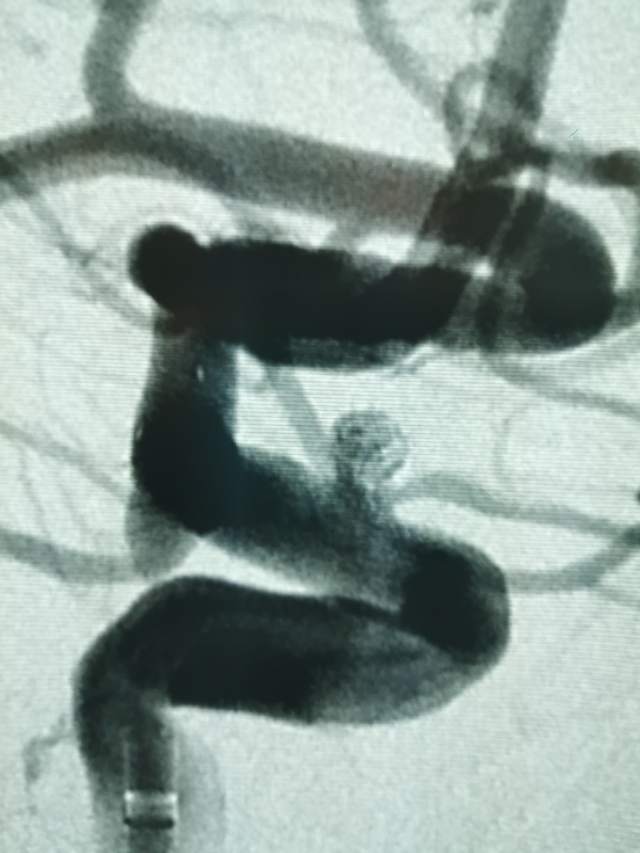

44岁盐城帅哥,因“头痛3天”发现静脉窦血栓合并“颅内动脉瘤“来诊。颅内动脉瘤之一是瘤体累及眼动脉的相对宽颈微小动脉瘤(2.5mm),此部位动脉瘤存在破裂出血的风险,而且静脉窦血栓的治疗也会加重此风险,有必要同步先消除这个潜在的风险。病变累及眼动脉,如果治疗过程中受到累及存在失明风险,需要重点保护。最终,采用一个支架一个圈的“简约模式:花费少,效果好”结束手术,眼动脉保留良好。